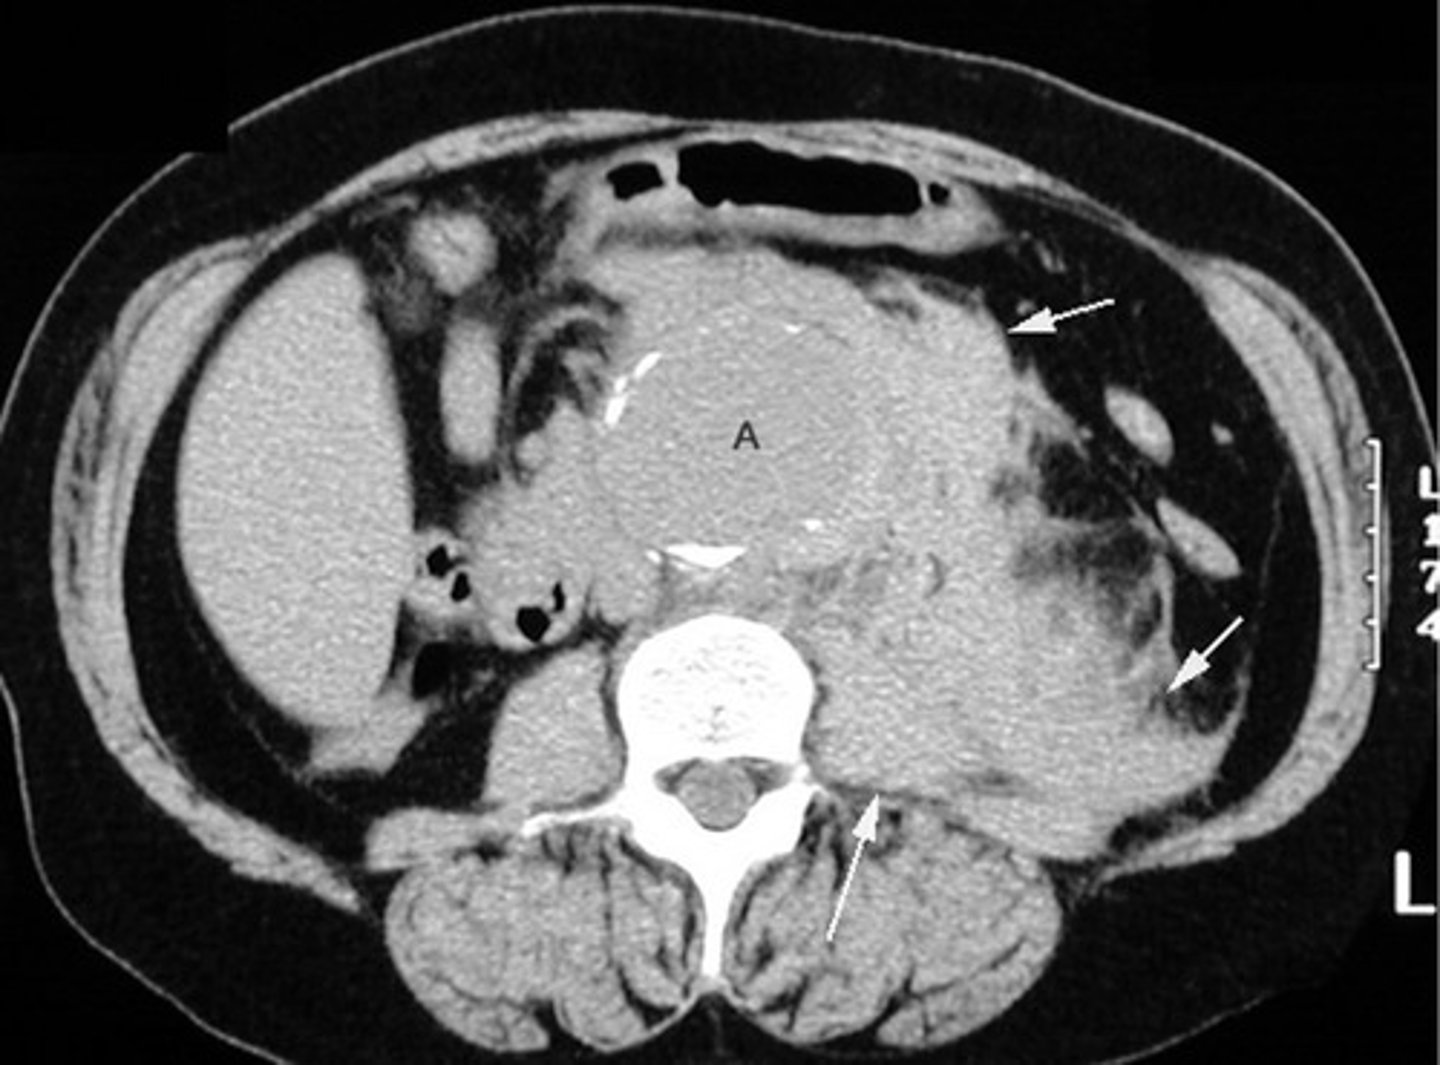

Abdominal aortic aneurysm on CT